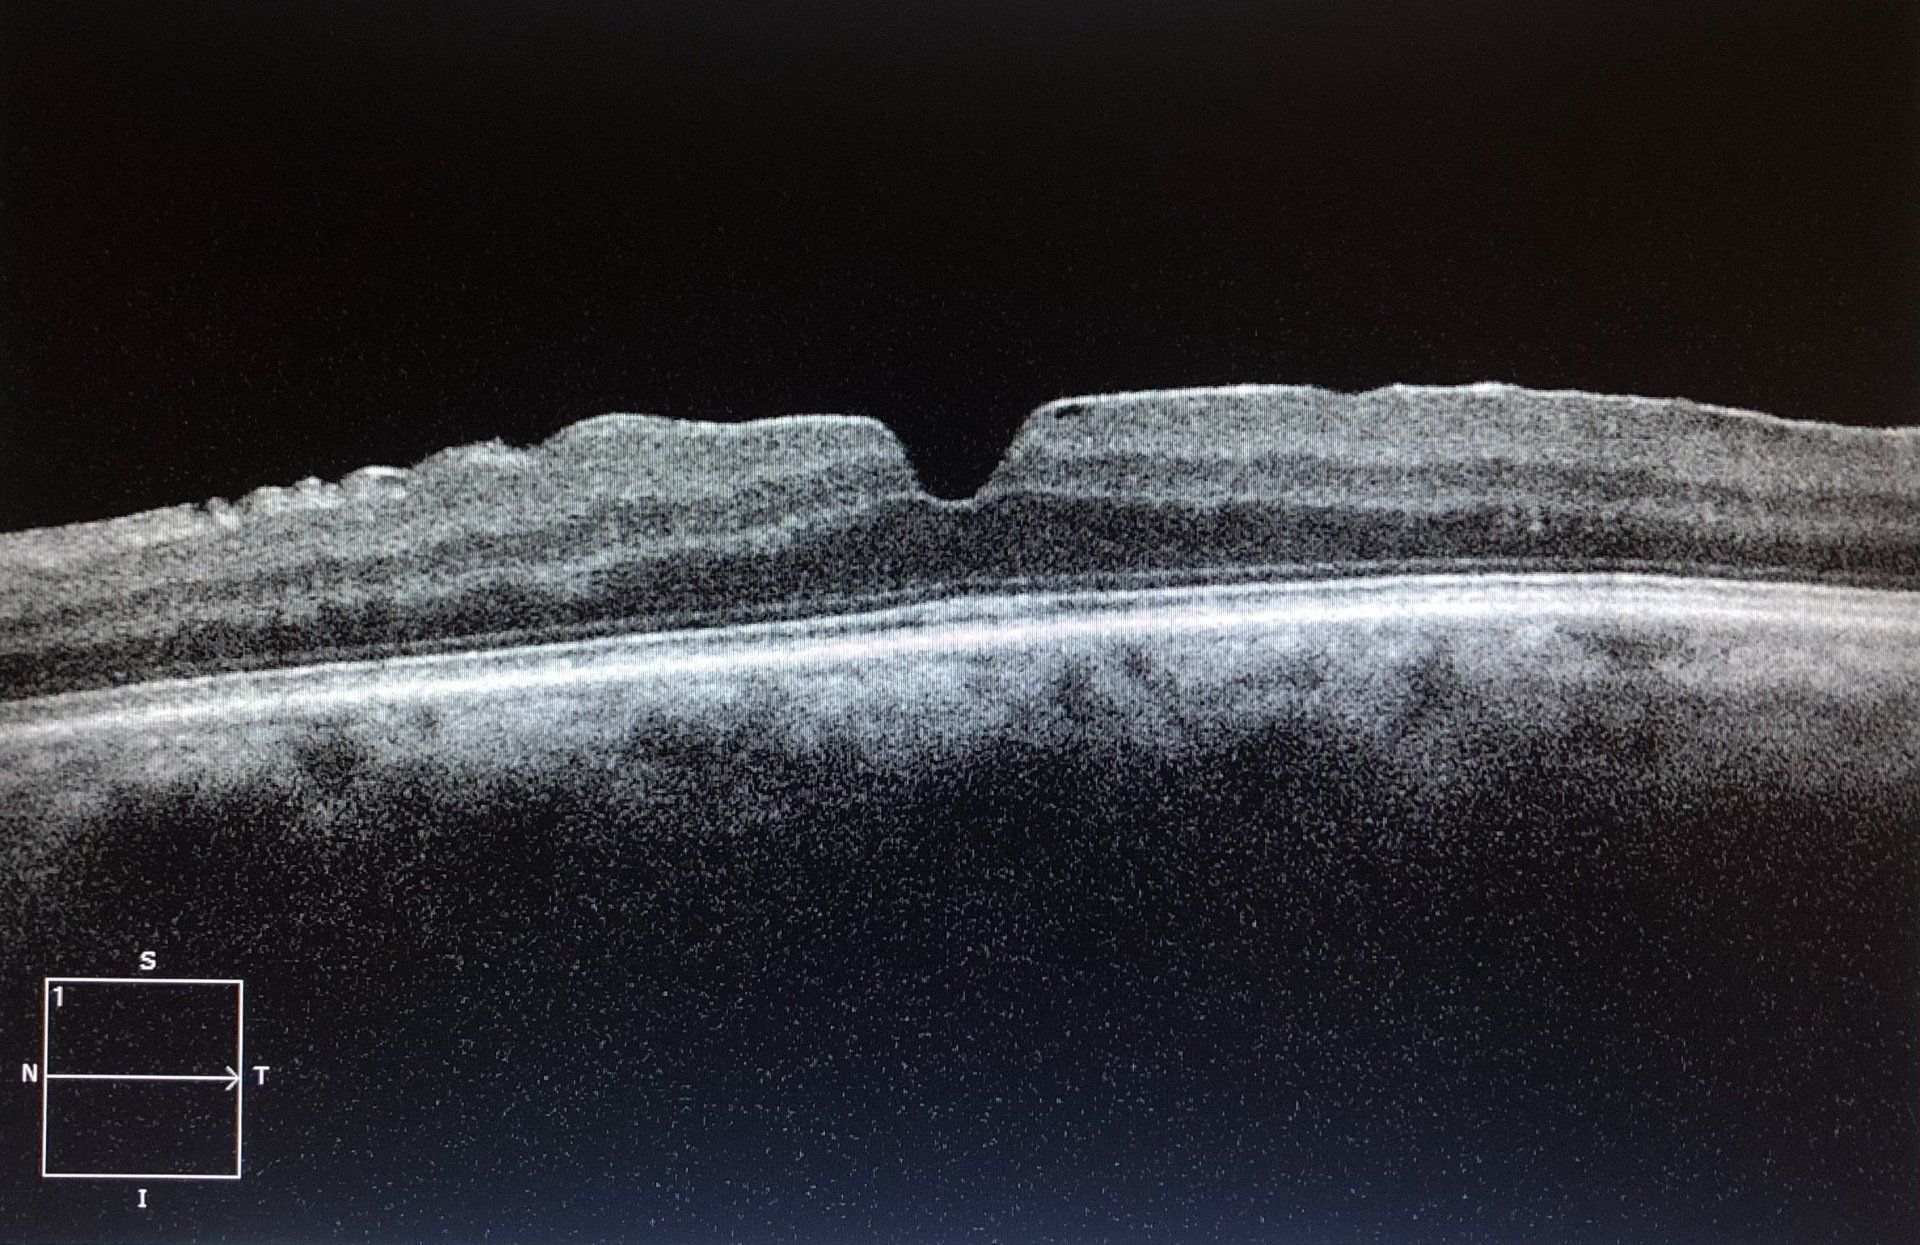

- OCT (Tomografia a Coerenza Ottica): mediante raggi infrarossi consente una ricostruzione ad alta definizione degli strati della macula. Questo esame evidenzia la presenza della membrana e il grado di trazione esercitata sulla retina, responsabile della riduzione della visione centrale e della distorsione delle immagini.